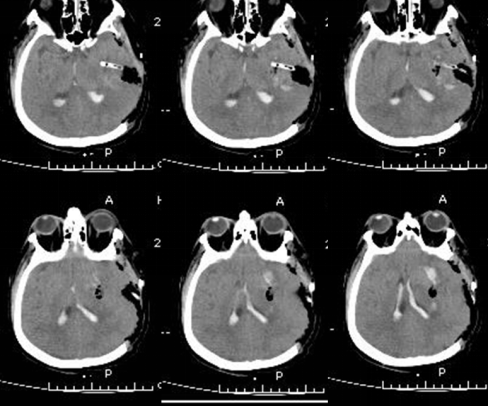

术前 术后3天

锥颅软通道置管引流具有微创、操作方便、血肿清除率高的优点